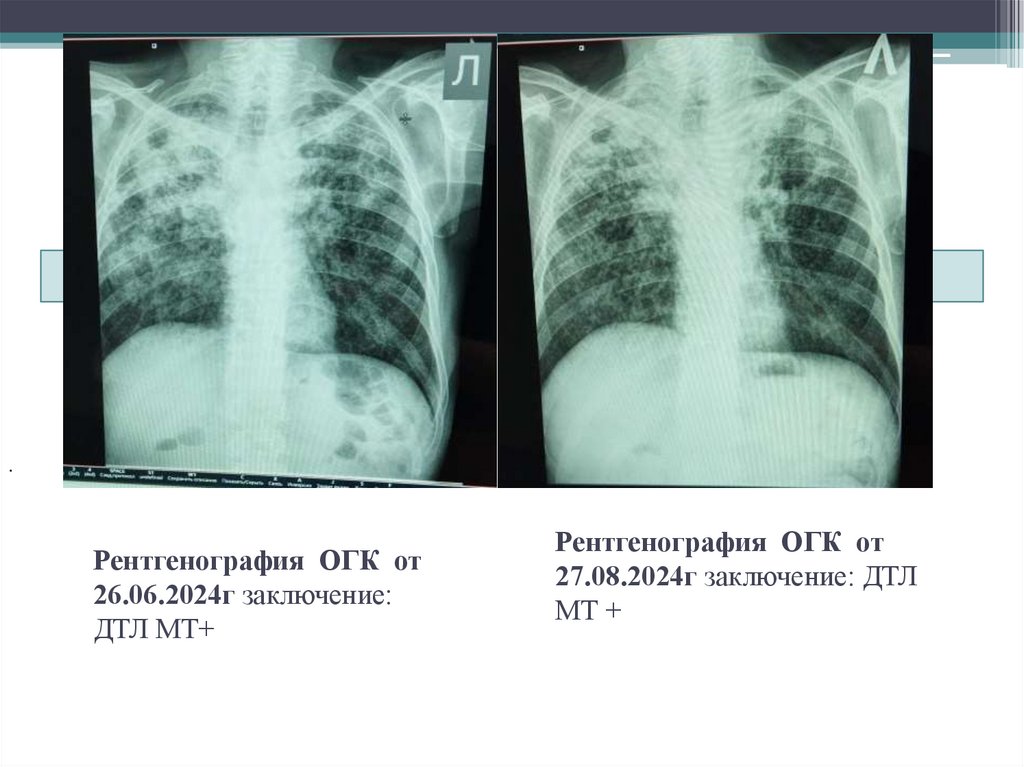

10. Рентгенография ОГК от 26.06.2024г заключение: ДТЛ МТ+

Рентгенография ОГК от

26.06.2024г заключение:

ДТЛ МТ+

27.08.2024г заключение: ДТЛ

МТ +